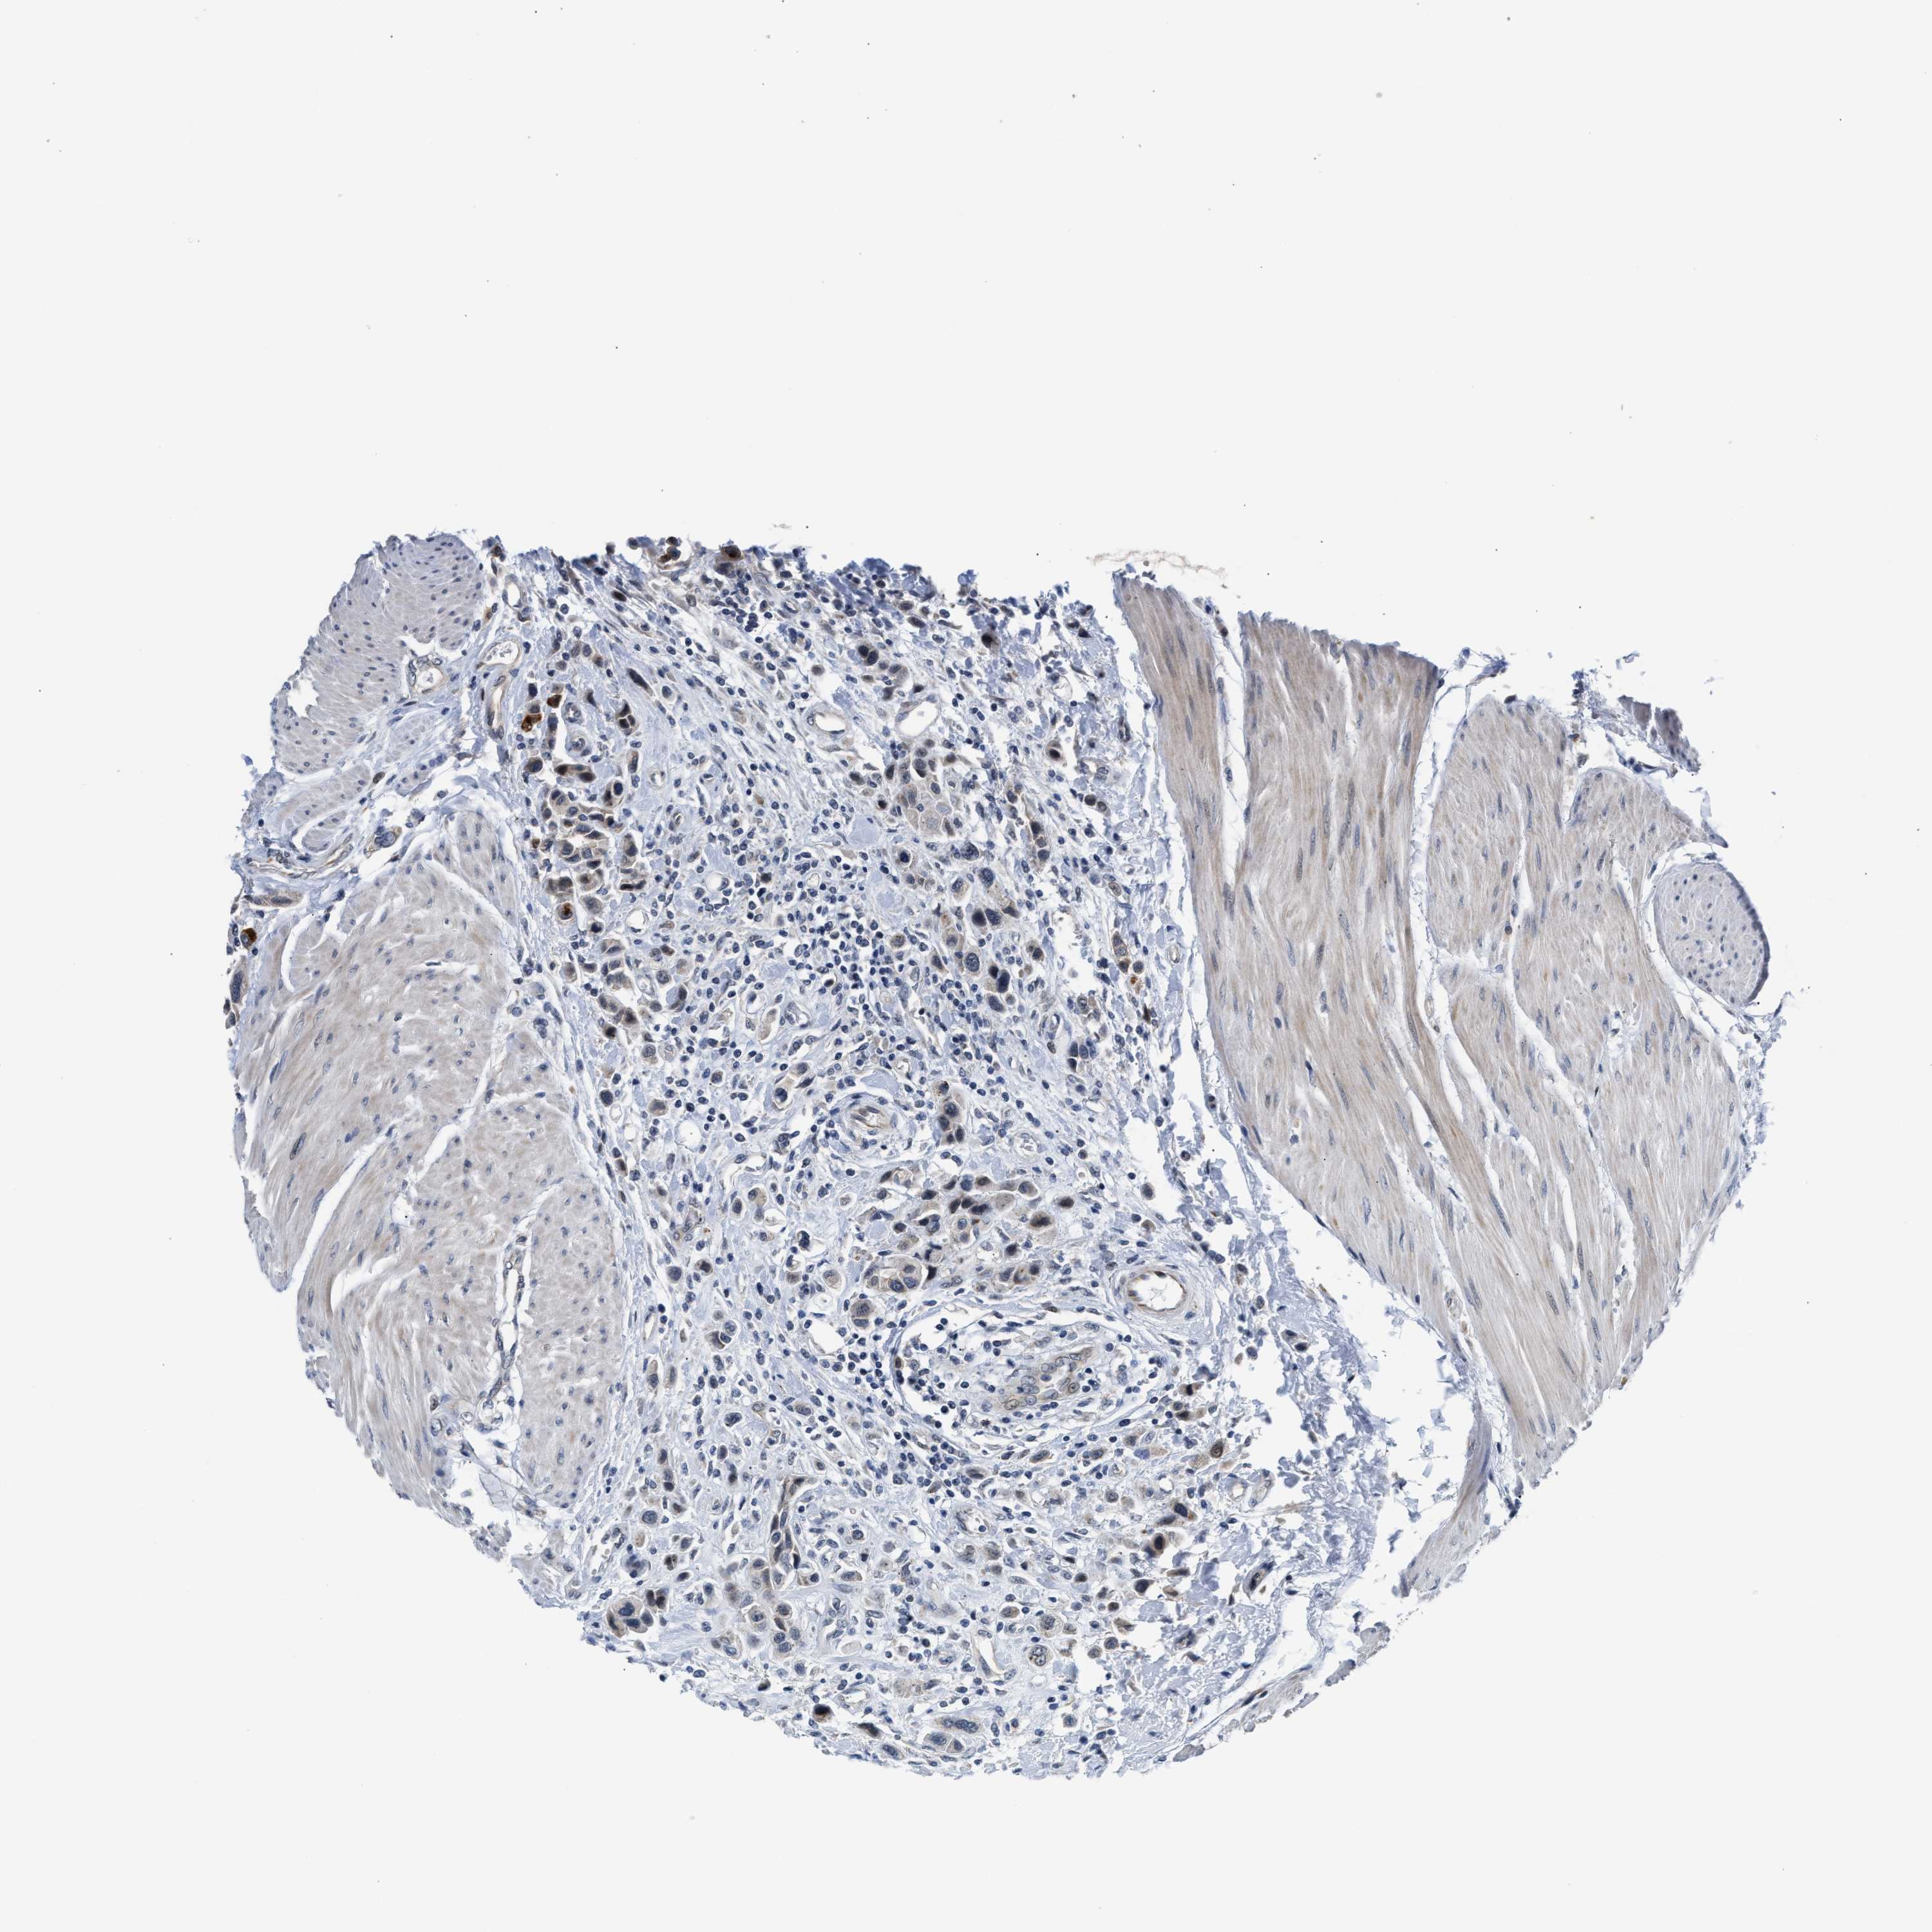

UROTHELIAL CANCER - Protein expressioni

A mouse-over function shows sample information and annotation data. Click on an image to view it in a full screen mode. Samples can be filtered based on level of antibody staining by selecting one or several of the following categories: high, medium, low and not detected. The assay and annotation is described here.

Note that samples used for immunohistochemistry by the Human Protein Atlas do not correspond to samples in the TCGA dataset.

Antibody stainingi

Antibody staining in the annotated cell types in the current human tissue is reported as not detected, low, medium, or high, based on conventional immunohistochemistry profiling in selected tissues. This score is based on the combination of the staining intensity and fraction of stained cells.

Each image is clickable and will lead to virtual microscopy that enables deeper exploration of all samples and also displays staining intensity scores, fraction scores and subcellular localization as well as patient and tissue information for each sample.

Antibody HPA044244

Antibody HPA058777

Antibody CAB020694

Staining

High

Medium

Low

Not detected

Intensity

Strong

Moderate

Weak

Negative

Quantity

>75%

75%-25%

<25%

None

Location

Nuclear

Cytoplasmic/membranous

Cytoplasmic/membranous,nuclear

Urothelial carcinoma, High grade

Urothelial carcinoma, Low grade

Urothelial carcinoma, NOS